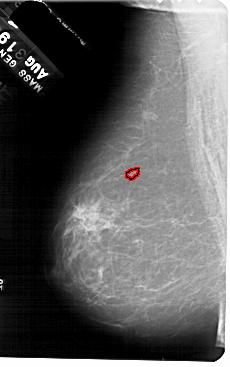

FILE: A_1552_1.LEFT_MLO.OVERLAY

TOTAL_ABNORMALITIES 1

ABNORMALITY 1

LESION_TYPE CALCIFICATION TYPE PLEOMORPHIC DISTRIBUTION CLUSTERED

ASSESSMENT 4

SUBTLETY 2

PATHOLOGY BENIGN

TOTAL_OUTLINES 1

BOUNDARY